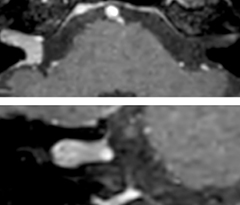

So, what is the actual impact of having more information and more diagnostic confidence? According to Dr. Savatovsky, “One of the indications I’ve seen where using Elition is most impactful is in patients with suspected giant cell arteritis. As an ophthalmologic hospital, we see many patients with suspected giant cell arteritis. Usually we were performing MRI to help us rule out an ischemic stroke, and to verify that the supra aortic vessels are undamaged. With Elition, we still do this, but now we can add on more detailed high-resolution black-blood sequences on superficial arteries. This provides us with high confidence levels for diagnosis of giant cell arteritis (GCA) and as a result, some patients are not sent for a biopsy anymore. A patient who has a normal MRI will not require a biopsy and can be discharged from the hospital in the same day. Before, such a patient would have to stay for about a week, just to find that their biopsy results were negative. We have at least three or four patients a week with suspected giant cell arteritis. For a great deal of these patients we can have a direct impact on their hospital stay.”

The 3D TSE T1w black blood MSDE sequence with fat suppression has an isotropic 0.8 mm voxel size and sagittal oblique and axial reformats are made. The images show superficial temporal artery thickening and peri-arterial fat infiltration. The 3D TSE PDw black blood MSDE with fat suppression has 0.55 mm isotropic voxels. The images shows focal involvement of the frontal branch of the superficial temporal artery.